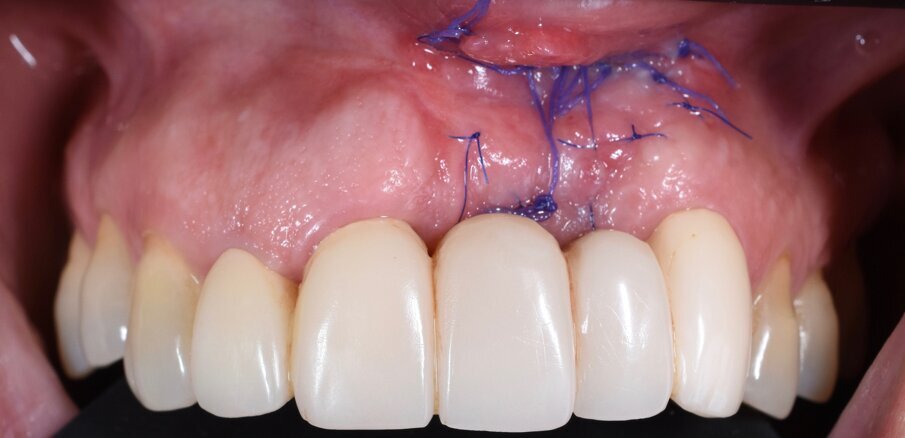

In questo articolo presentiamo un caso clinico che dimostra come il posizionamento improprio di un impianto può rendere impossibile la riabilitazione protesica, che richiede una nuova pianificazione chirurgica e riabilitativa per ottenere l’estetica desiderata. La paziente si presenta alla nostra osservazione con una riabilitazione protesica incongrua, con flangia in resina, a supporto dentale ed implantare, con la presenza di un impianto in posizione 2.1 vestibolarizzato e con l’emergenza nel fornice, in mucosa alveolare. Dalla valutazione della Tac si evince la posizione errata dell’impianto e la perdita consistente in senso trasversale della compagine ossea (Figg. 1, 2). Pertanto si opta per il seguente piano di trattamento che prevede: rimozione dell’impianto e preparazione protesica dell’elemento 2.3, confezionamento di un primo provvisorio a supporto dentale che servirà a guidare la guarigione dei tessuti (Figg. 3-7). A distanza di 4 mesi si procede a un innesto epitelio connettivale libero con prelievo dal palato per compensare il gap dei tessuti molli in senso trasversale, quindi viene ribasato il provvisorio in modo tale da favorire la guarigione dei tessuti (Figg. 8-11). A 9 mesi dalla maturazione dei tessuti si procede alla finalizzazione protesica fissa a supporto dentale (Figg. 12-14).

Fig. 7 - Applicazione del provvisorio dopo preparazione protesica del 2.3 e frenulectomia laser.

Fig. 11 - Controllo a 3 settimane dall’innesto.

Fig. 14 - Finalizzazione protesica.